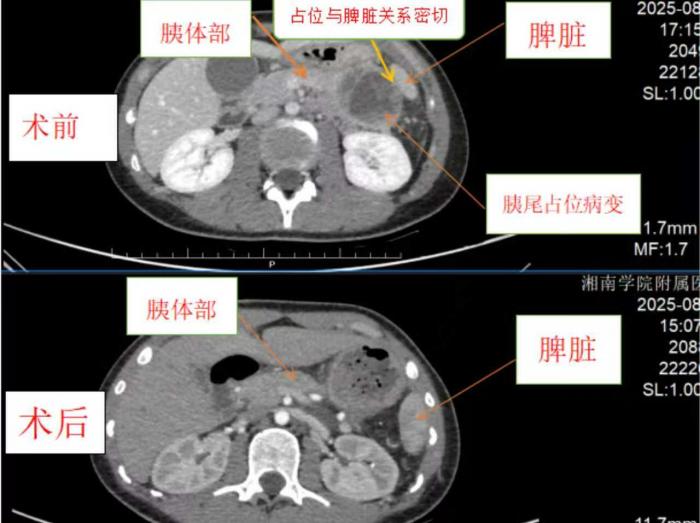

在湘南学院附属医院治疗期间,女孩病情出现波动,反复腹痛、呕吐腹泻,还合并极度营养不良,家属十分焦虑。科主任彭钊主任医师、何松副主任医师高度重视,多次查看患者、翻阅病历,经全面评估,明确诊断后判断患者有外科手术指征,且无明显手术禁忌证。彭钊主任带领团队反复研讨,决定为患者实施全麻腹腔镜下胰尾占位切除术(备联合脾脏切除术),力求在切除肿瘤的同时保住脾脏。

8月8日,手术如期开展。彭钊主任带领团队操作腹腔镜,术中发现胰尾肿物约6×5×3cm,团队精准分离组织、处理血管,成功切除肿瘤,还保住了脾脏。术后标本送检,病理结果确诊为胰腺实性-假乳头状瘤,与术前诊断一致。